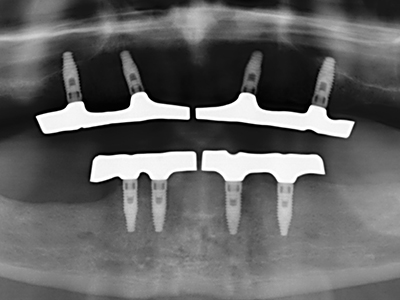

En la extracción de bloques óseos la piezocirugía también presenta ventajas adicionales: Además de la alta precisión en la osteotomía que ya se ha descrito antes, se ha comprobado que el uso de los delgados insertos de sierra resulta especialmente cuidadosas con el hueso. Frente a esto, sobre todo cuando se usan las fresas de Lindemann, cabe esperar pérdidas en la extracción significativamente más altas debido al mayor grosor de la parte frontal del cabezal (Lakshmiganthan, Gokulanathan et al. 2012). La separación basal que se necesita en particular en los injertos de bloque extraídos de forma retromolar se ve facilitada mediante sierras perpendiculares especialmente previstas a tal fin, lo que permite considerar que la cirugía piezoeléctrica es un procedimiento preciso y seguro para la obtención de bloques de hueso en el área retromolar (Happe 2007) (fig. 1-12).